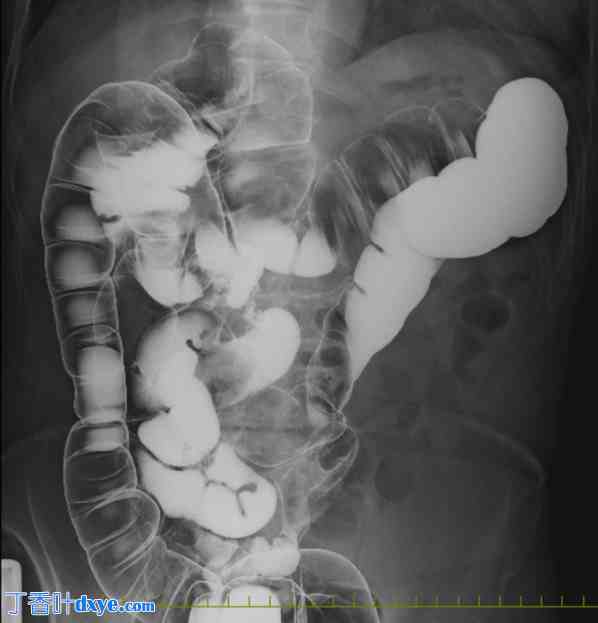

图 2.

灌肠检查。降结肠至乙状结肠在右侧走行